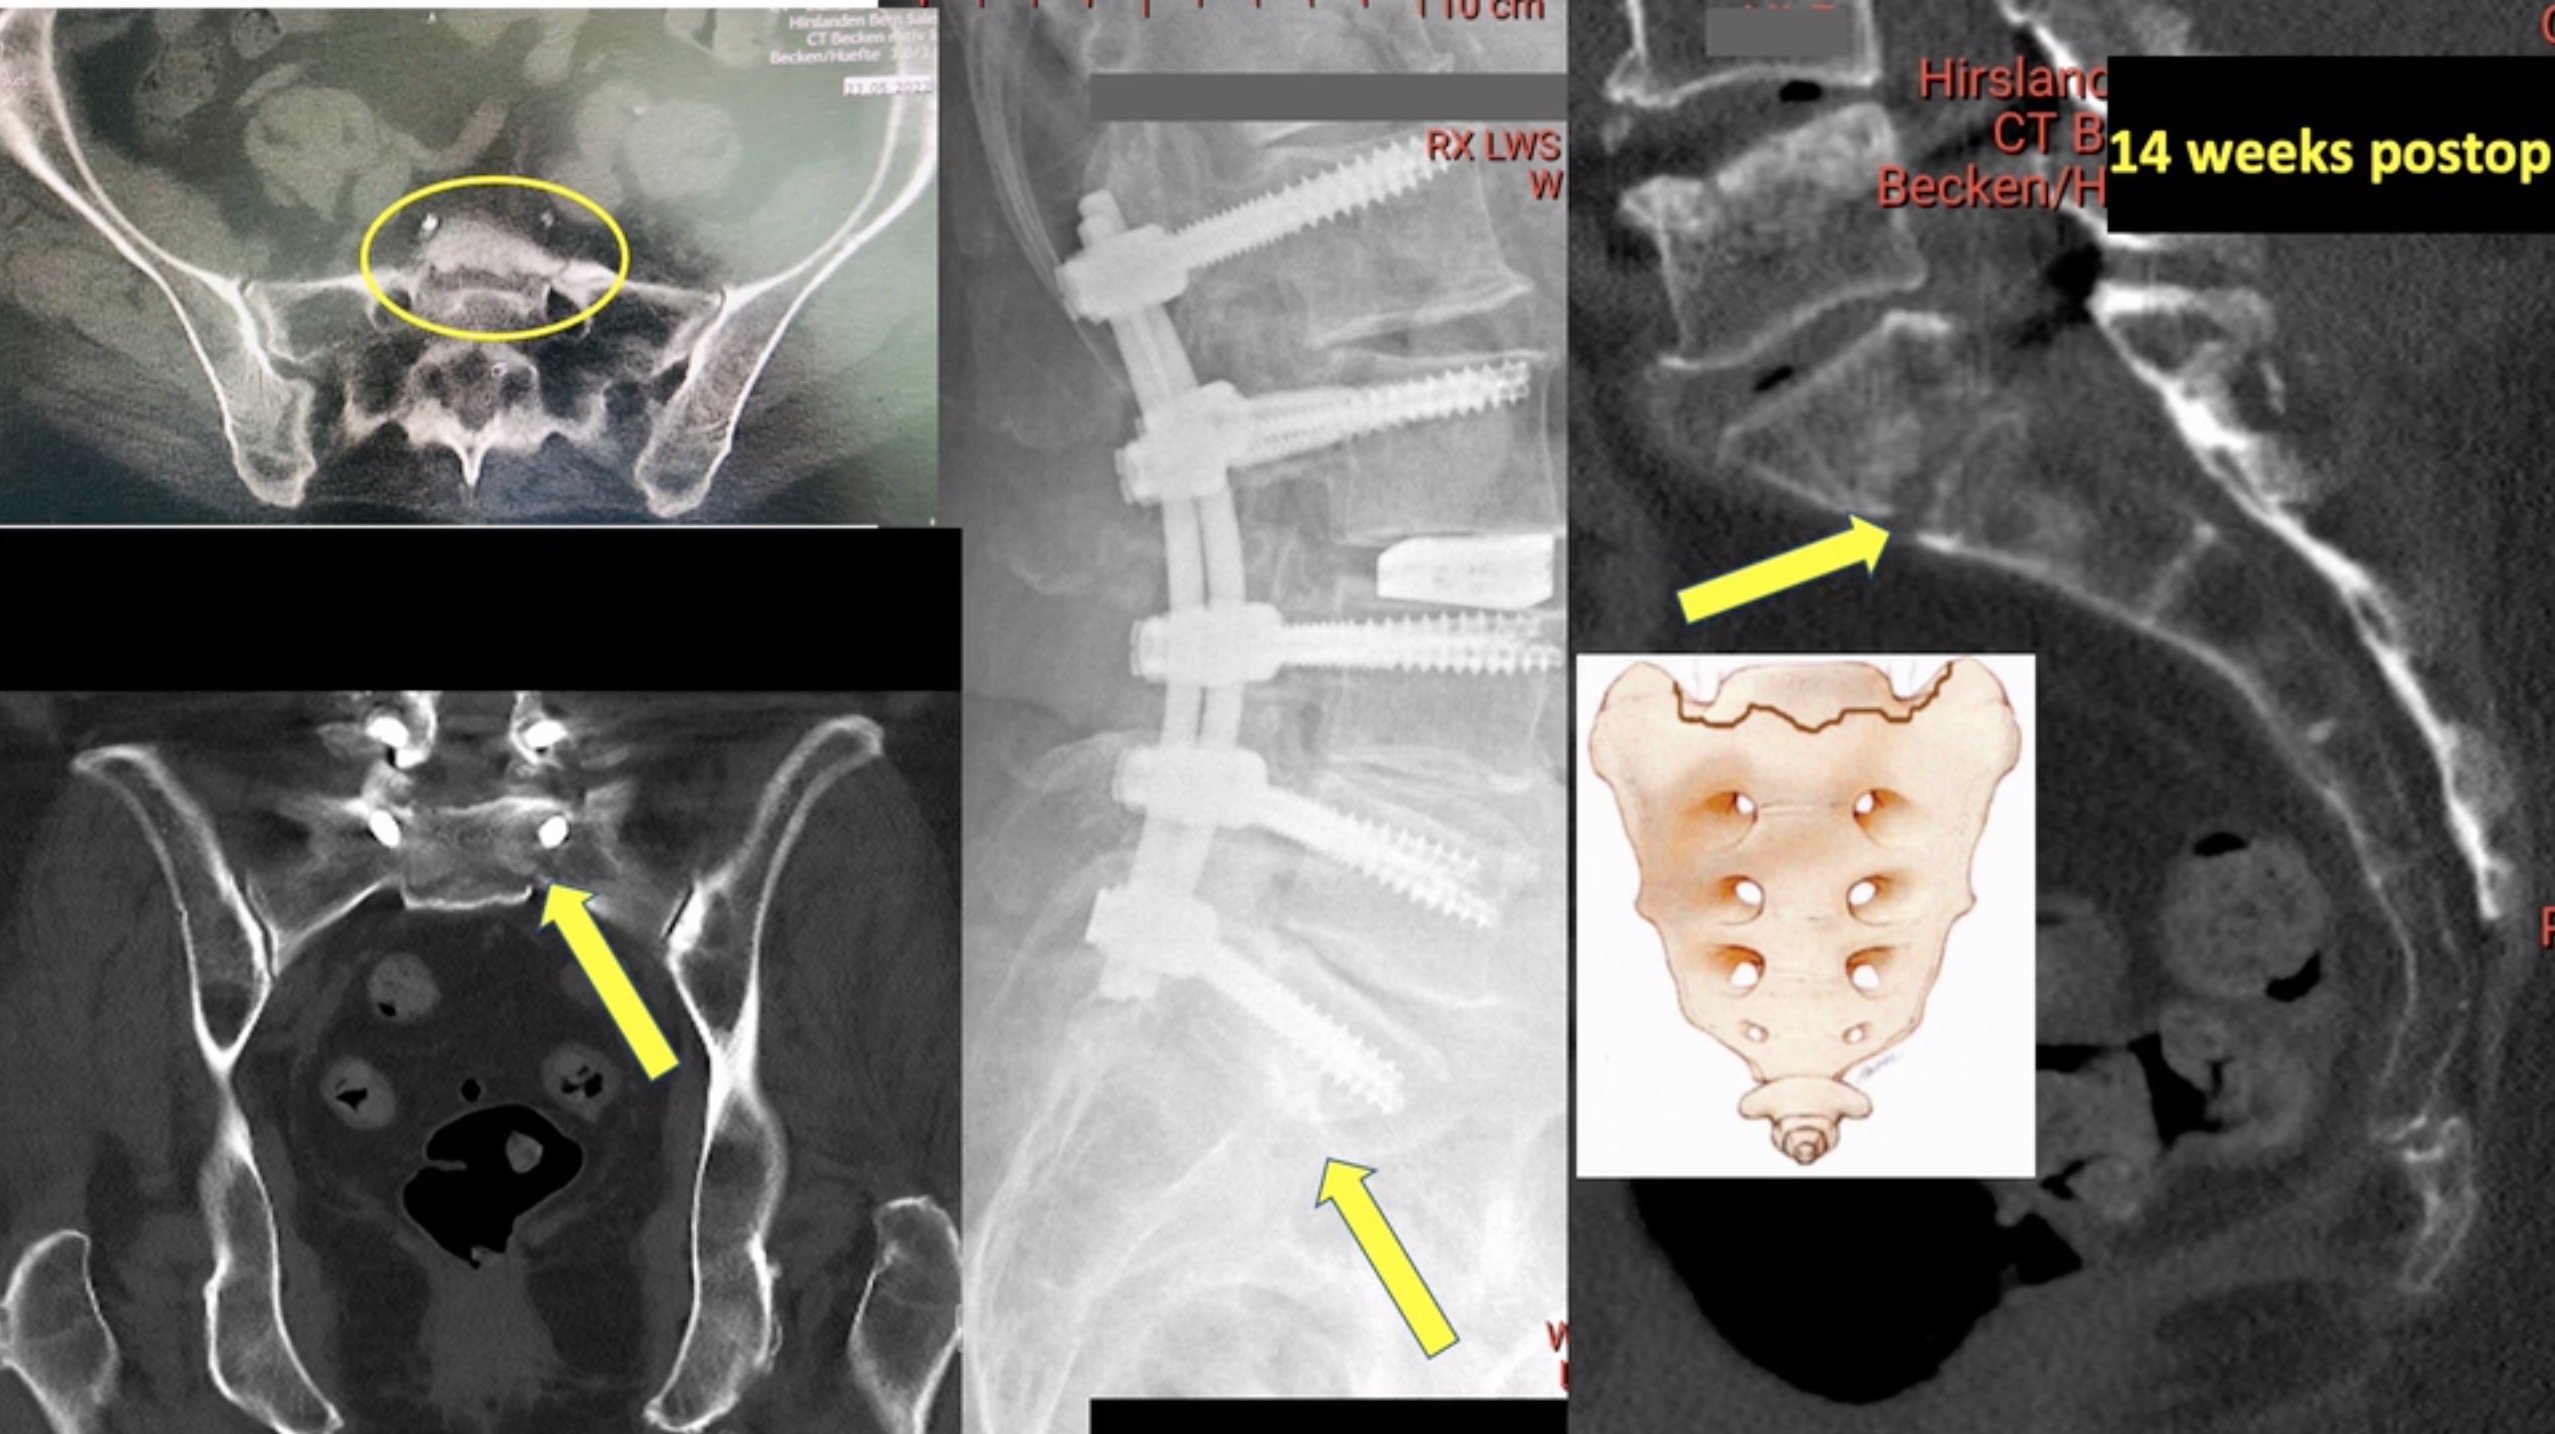

Trailer Surgery for distal junctional failure with pelvic pull-out and ALIF cage

Watch the full Video

Project 23-003 -